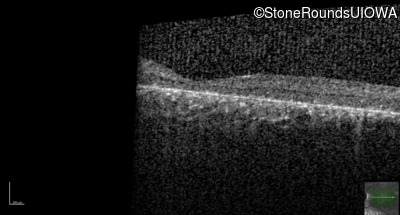

Age at visit: 8 years

This 8 year old girl had normal vision until age 6 when she failed a school vision screening. That year, she was able to play softball well, but this year she often loses sight of the ball and is often hit by it.